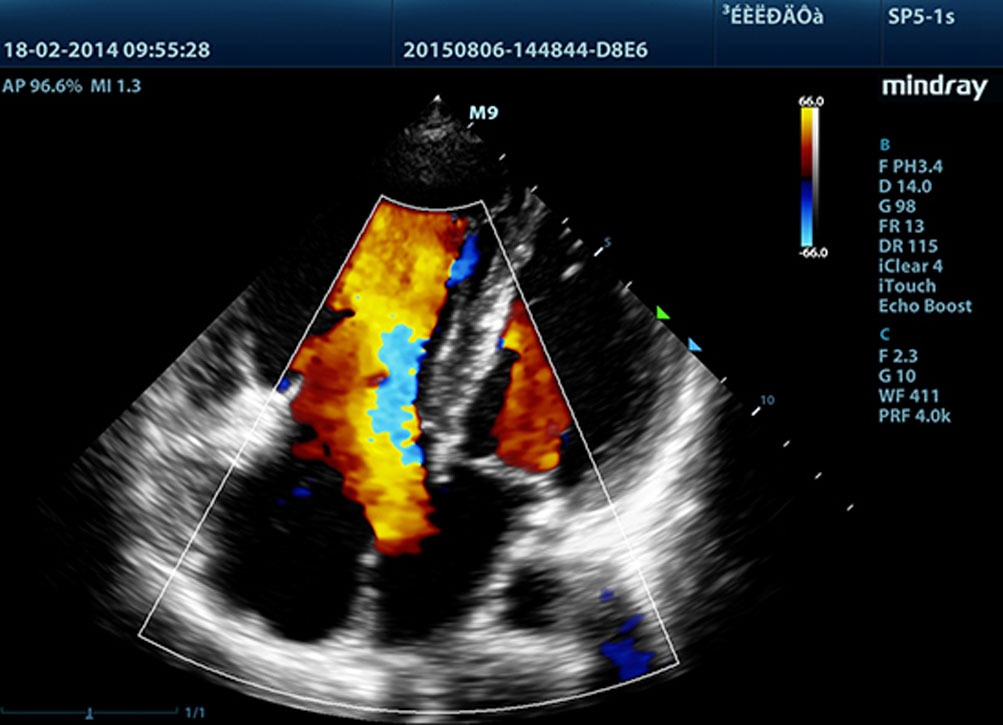

LVO met Stress Echocardiografie

De sterke functionaliteit van de M9 maakt opacificatie van de linker ventrikel onder stress mogelijk, waardoor beter onderscheid kan worden gemaakt tussen hartspierweefsel en bloedvolume, wat een betere weergave geeft van endocardiale oppervlakken. De Stress Echo functie van de M9 biedt een complete oplossing voor echoŌĆÖs onder farmacologische- of inspanningsstress. De oplossing wordt ondersteund door een flexibel rapportagesysteem dat naar persoonlijke behoefte aangepast kan worden.